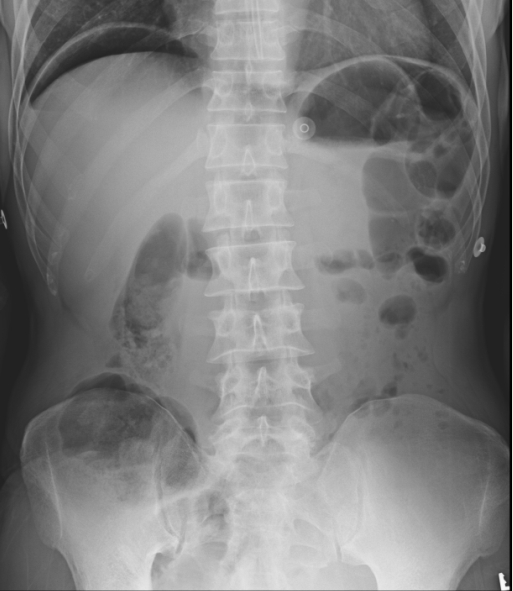

54F presents to ED d/t 5hr hx of diffuse severe abdo pain w/ n/v. She reports that 2wks ago she began to have mild epigastric pain that improved with eating. PMHx of OA, controlled with ibuprofen for years. Social drinker.

AXR is shown below.

What is the most likely cause of her current symptoms?

A

(E) - epigastric pain that gets better with eating -> duodenal ulcer, which causes the perf seen in the axr w/ free air under dphram